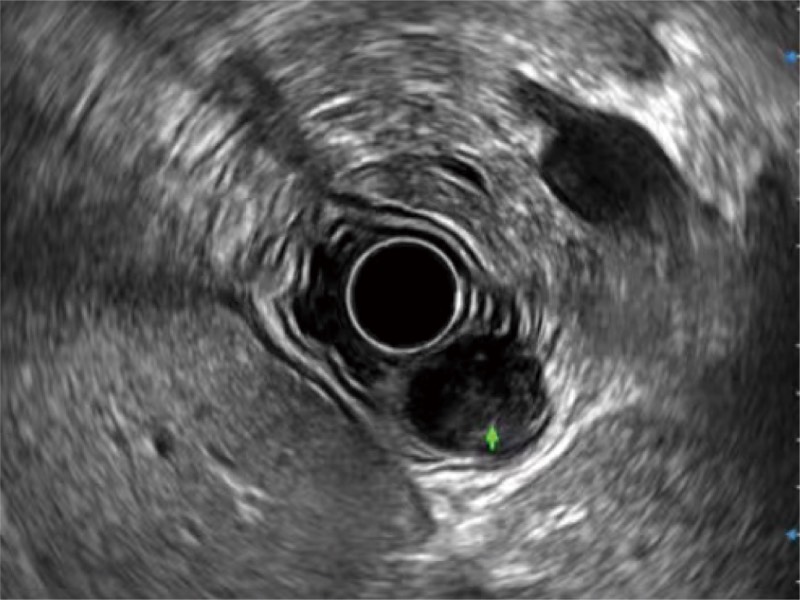

• 食管内间质瘤清晰显像

• 肝左叶和肝静脉的横截面